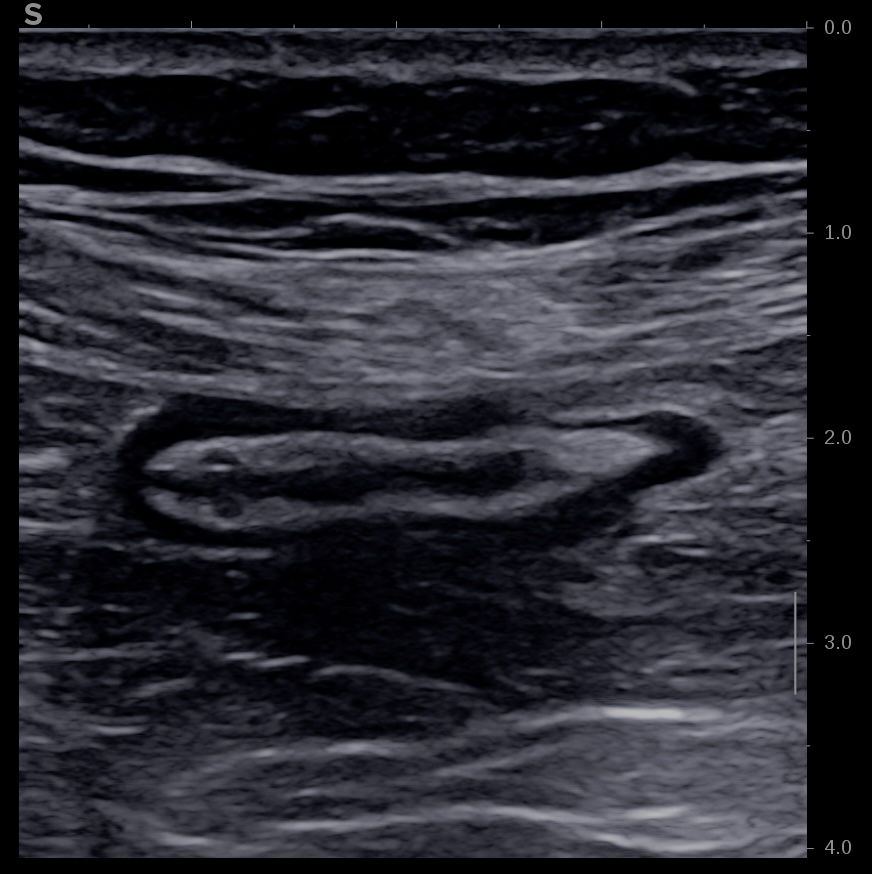

Ci dessous même portion avec et sans compression douce.

Il faut faire la moyenne de plusieurs mesures (≥3) en coupe longitudinale et transversale